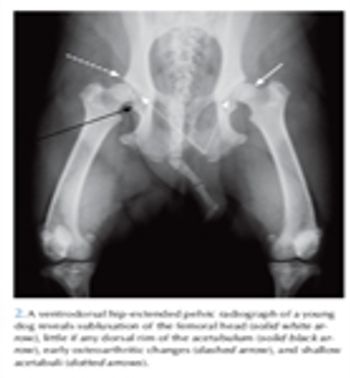

For too long, many veterinarians who have diagnosed hip dysplasia in young patients have informed the owners that the consequences will have to be dealt with later in life, when signs of osteoarthritis develop.